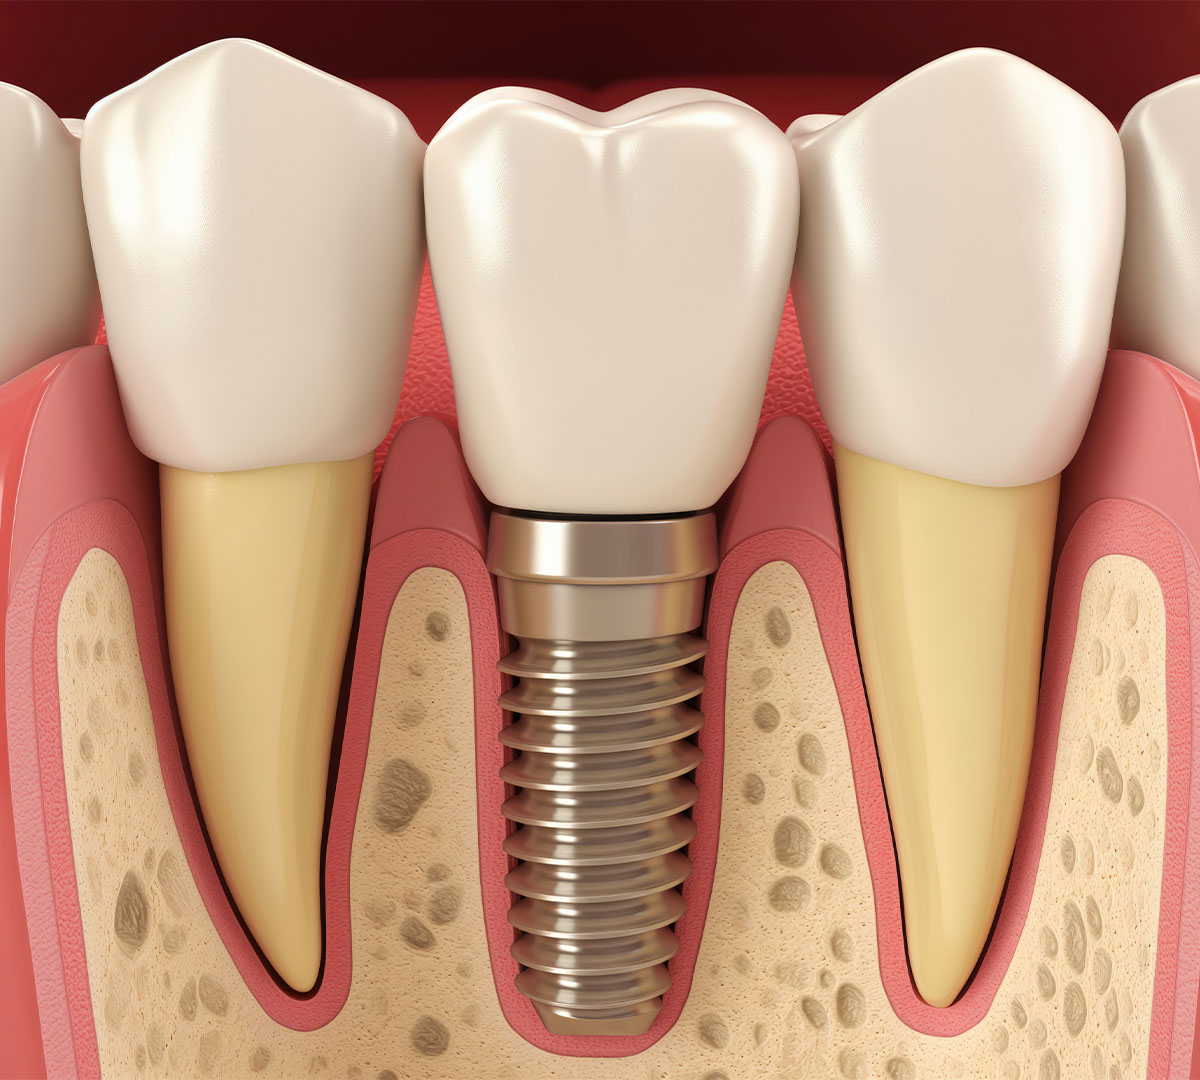

Qu’est-ce qu’un implant dentaire ?

Un implant dentaire est une vis en titane insérée dans l’os de la mâchoire pour remplacer la racine d’une dent manquante. Ce dispositif permet de fixer solidement une prothèse dentaire, qu’il s’agisse d’une couronne, d’un bridge ou d’une prothèse amovible stabilisée.

Grâce au processus d’ostéointégration, l’implant fusionne avec l’os, offrant un ancrage stable et résistant aux forces de mastication. Cette solution présente plusieurs avantages :

2. La chirurgie implantaire

Sous anesthésie locale, le chirurgien insère l’implant dans l’os en respectant des protocoles stricts d’asepsie. La présence d’un bloc opératoire est recommandée pour garantir une sécurité optimale.

3. L’ostéointégration

Cette phase dure entre 3 et 6 mois, le temps que l’implant s’intègre parfaitement à l’os de la mâchoire. Cette période est essentielle pour assurer la stabilité à long terme de l’implant.

4. Pose de la prothèse dentaire

Une fois l’ostéointégration confirmée, une prothèse sur-mesure est fixée sur l’implant. Selon les besoins du patient, il peut s’agir :

- D’une couronne unique pour remplacer une dent isolée.

- D’un bridge pour remplacer plusieurs dents.

- D’une prothèse amovible stabilisée sur plusieurs implants.